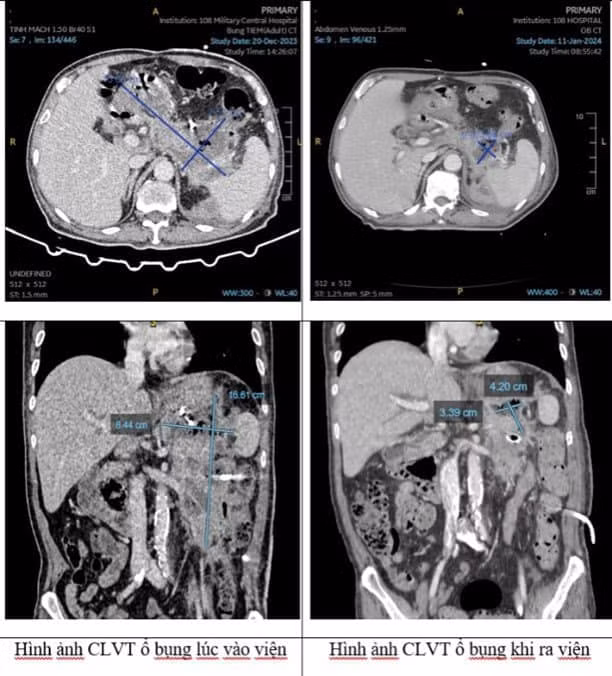

Bệnh nhân nhập viện trong tình trạng toàn thân suy kiệt nặng, sốt cao liên tục 39 độ C và có nhiều cơn rét run. Kết quả chụp CLVT ổ bụng thấy nang tụy hoại tử kích thước lớn 15,6cm x 16,6cm x 7,6cm có nhiều khí và tổ chức hoại tử rắn trong nang, cấy dịch hoại tử tuỵ thấy nhiễm vi khuẩn Klebsiella aerogenes đa kháng.

Sau 3 lần đưa ống soi vào lấy tổ chức tụy hoại tử kết hợp với bơm rửa hàng ngày, bệnh nhân được xuất viện sau 20 ngày điều trị trong tình trạng hết sốt, ăn uống, tự đi lại được, trên kết quả xét nghiệm marker viêm về bình thường. Hình ảnh chụp CLVT ổ bụng cho thấy ổ hoại tử tụy đã thu nhỏ rất nhiều so với trước điều trị.